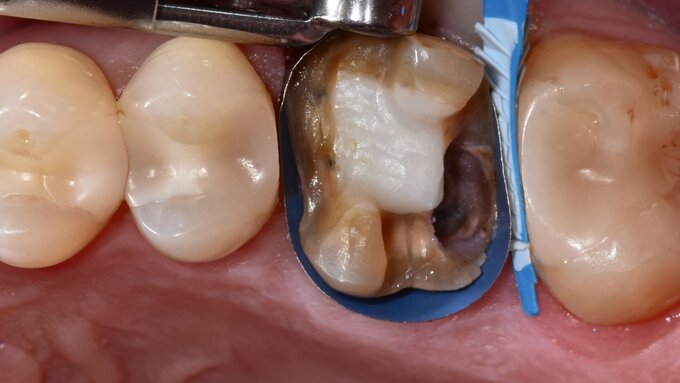

Aufgrund einer erwartungsgemäß erschwerten fotografischen Dokumentation bei der zahnärztlichen Behandlung in der mobilen Zahnmedizin wird die klinische Falldokumentation an einer Seniorin vorgenommen, deren Therapiefähigkeit und Eigenverantwortlichkeit nicht eingeschränkt war. Die 76-jährige Patientin stellt sich zur routinemäßigen Kontrolle in der Poliklinik für Zahnerhaltungskunde vor. Die allgemeine Anamnese ergab Zustand nach Meningeom, eine Quecksilber- und eine Birkenpollenallergie und einen erhöhten Blutdruck, der mit Lercanidipin eingestellt war. Am circa 20 Jahre alten Gussmetall-Inlay an Zahn 24 wurde dabei ein sondierbarer Randspalt festgestellt (Abbildungen 2a und 2b).

Nach Reinigung der Zähne und Bestimmung der Zahnfarbe wurde Kofferdam zur absoluten Trockenlegung angelegt. Mit rotierenden Instrumenten wurde ein Teil des Gussmetall-Inlays im sondierbaren Bereich entfernt und die Karies exkaviert (Abbildungen 2c und 2d). Anschließend wurden alle zu reparierenden Oberflächen (Gussmetall, Dentin und Schmelz) mit reinem Aluminiumoxid, Partikelgröße 50 µm (Rondoflex®/KaVo), unter Verwendung von Wasser abgestrahlt und danach gründlich mit Wasser abgespült (Abbildungen 2e und 2f). Die selektive Schmelzätzung erfolgte mit 37,5-prozentiger Phosphorsäure (Email Preparator®/Ultradent) für 30 Sekunden (Abbildung 2g). Nach Abspülen der Phosphorsäure mit Wasser wurde ein Universaladhäsiv (Clearfil Universal Bond Quick® / Kuraray Noritake) aufgetragen (Abbildung 2h, Glanz soll erhalten bleiben, Verdunstung einige Sekunden abwarten) und dann lichtpolymerisiert.

Im Anschluss wurde die Reparaturrestauration mit Komposit (Ceram X Spectra®/Dentsply Sirona) eingebracht (Abbildung 2i). Im Sinne des Restaurationsunterhalts wurden bei der Politur die Restaurationsränder der Gussmetall-Inlays an den Zähnen 24 und 25 finiert und zusammen mit der Kompositrestauration hochglanzpoliert (Abbildungen 2j und 2k).